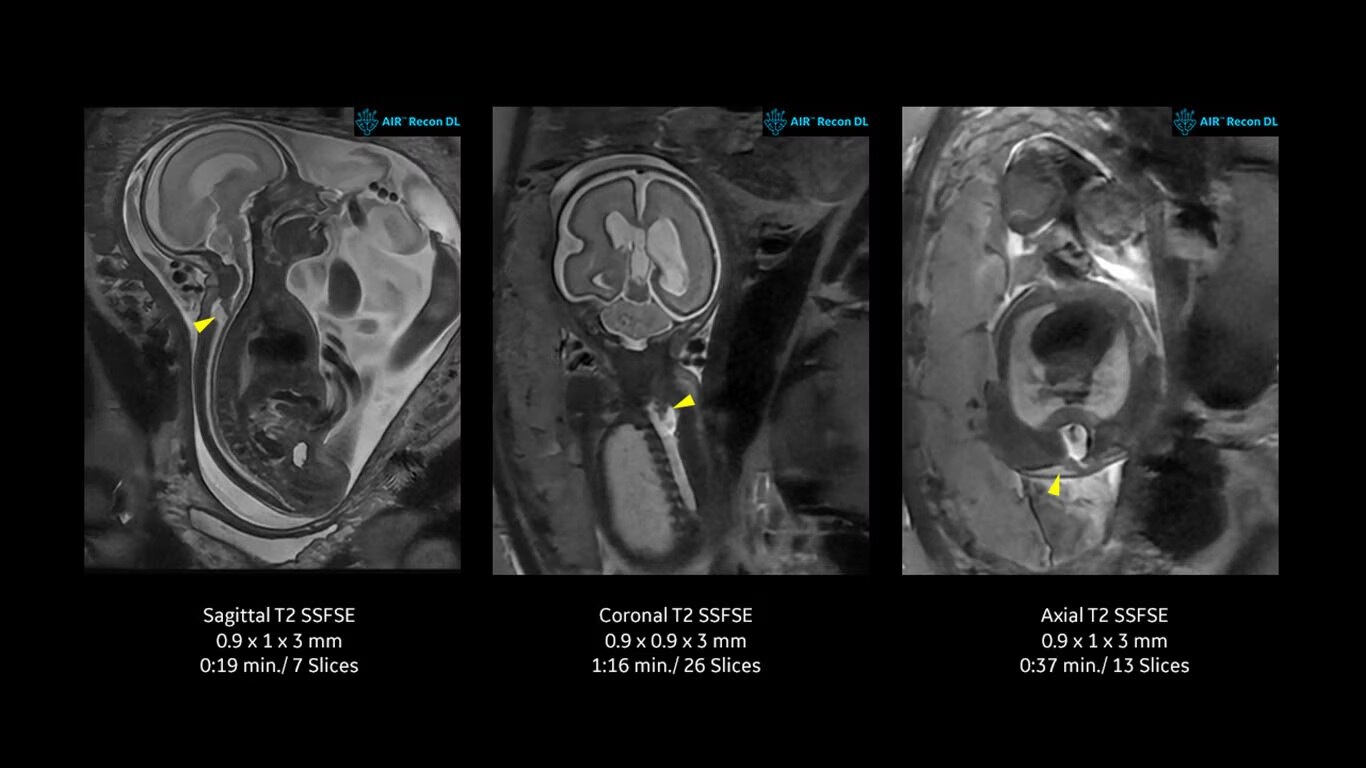

SIGNA™ Artist 1.5T MRI scanner provides 360-degrees of coil coverage, RF technology, and a direct digital interface with more channels. Patient-friendly design maximizes comfort and system utility, accommodating all types of patients and sizes with feet-first imaging. Combined with our industry-leading, deep-learning technology, AIR™ Recon DL, you can achieve consistent, exceptional images 50% faster;* streamlining workflows and reducing patient table time.

MR image reconstruction with AIR Recon DL

Evolve your MRI scanner's capabilities: experience exceptional image quality without compromising scan time.